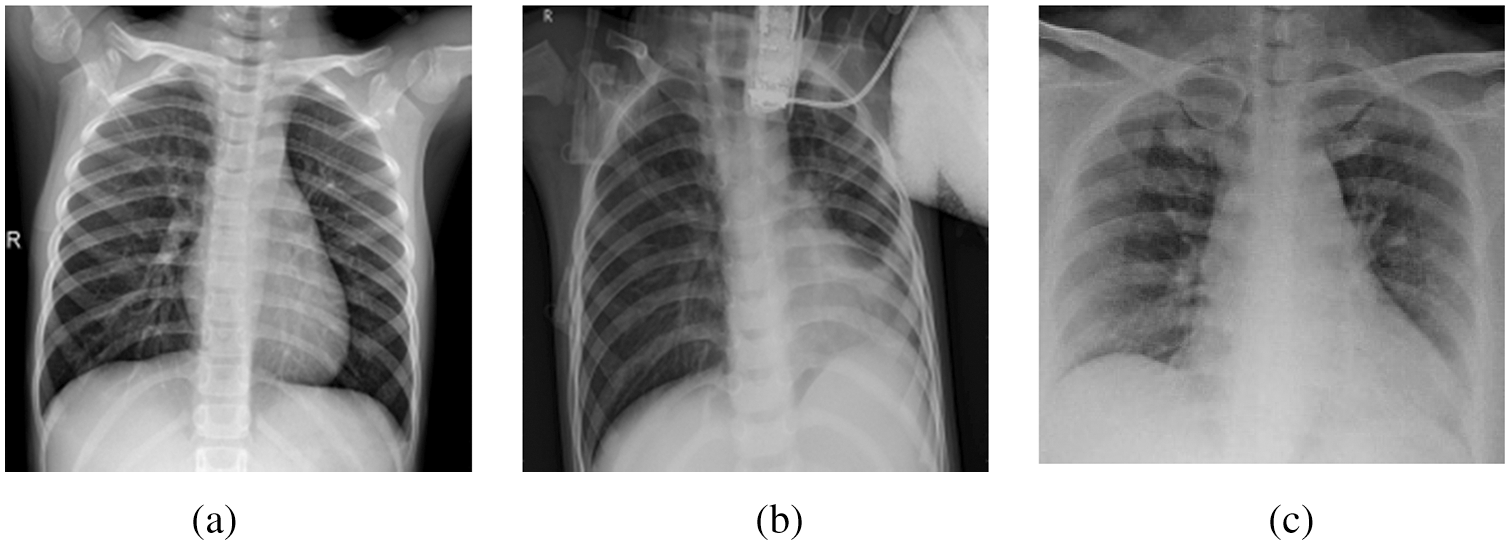

This section presents the initial phase of the research methodology, which is the data preparation phase. The availability of datasets is volatile. In general, publicly available datasets for COVID-19 patients to train machine learning models and obtain excellent results are still limited. In this work, many X-ray thoracic images were collected to train the proposed COV2Net model, as described later. The constructed dataset contains three classes of patients: normal patients, COVID-19-confirmed patients and patients with other pneumonia types. Fig. 2 shows examples of each category.

Figure 2: A sample of image classes in the collected dataset: (a) Normal case, (b) Pneumonia case, (c) COVID-19 case

The X-ray images obtained from many publicly available sources were filtered and resized as valid images. As a result, 1349 images of normal patients and 3895 images of non-COVID-19 related pneumonia cases were collected. This part of our dataset originated from two different datasets, the Joseph Paul Cohen database, and Dataset-01 Chest X-rays. In addition, the COVID-19-based X-ray images required four different databases to collect 1764 images. The details are illustrated in Table 2.